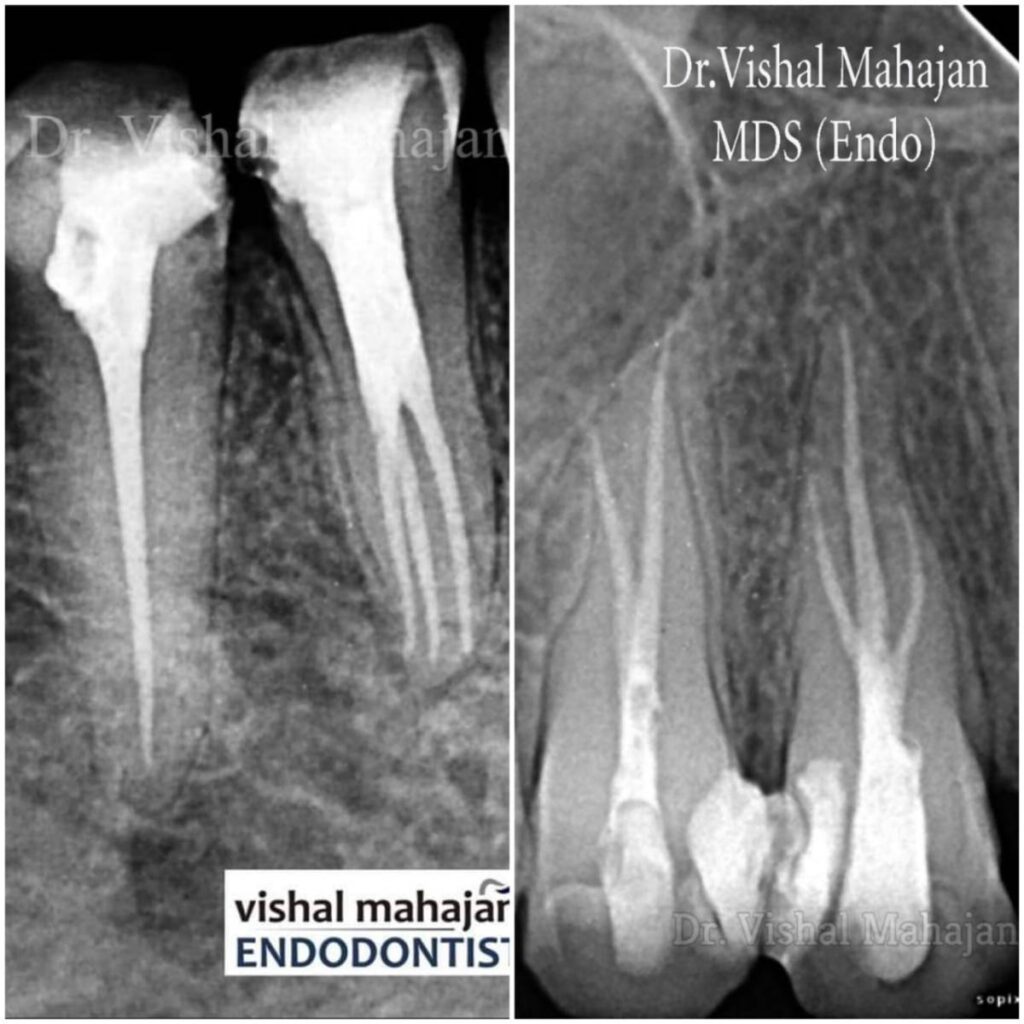

Root Canal Treatment

Single Visit Root Canal

A Single Visit Root Canal Treatment (RCT) is a modern dental procedure where the entire root canal process is completed in just one appointment.

Dental Microscope

A Dental Microscope is an advanced tool used in modern dentistry to provide high magnification and better visibility, especially during precise treatments like Root Canal Therapy.

- We use the latest dental technology including digital X-rays, intraoral scanners, loupes, and laser treatments.